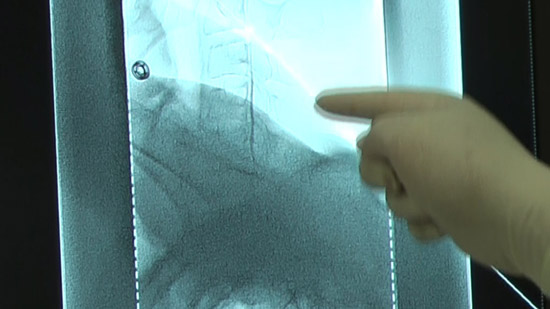

(2)穿刺部を透視画面と合わせて確認し、位置決めを行う。

(4)抵抗消失法にて硬膜外穿刺を行う、透視画面で確認。

※造影剤を注入し更に確認。同時に確認画像を撮影。

透視画面で確認。

今回は10cc注入時に患者さんに自覚体調を確認、更に投影画像を撮影。

注入終了時に投影画像を撮影。